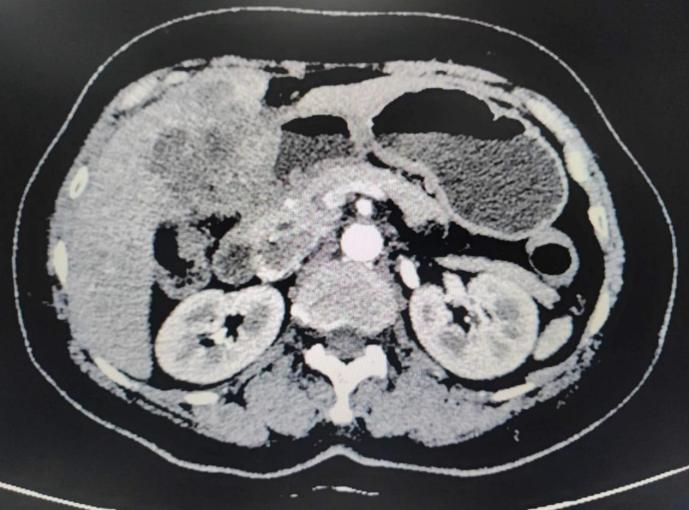

患者徐女士因右上腹阵发性疼痛1周,就诊于南溪山医院。腹部彩超、上腹部CT、磁共振、穿刺活检等检查提示肝占位性病变(胆囊癌肝转移可能)。住入肝胆胰脾外科后,科室负责人杨志坚、副主任黄芳详细询问患者病情,仔细查看影像学资料,确认患者胆囊癌肝转移可能,未见远处转移,有完整切除可能。患者肿瘤较大近10cm位于肝门部占位效应明显,且可能侵犯胃窦、十二指肠。

手术团队充分评估手术风险后,详细制定了手术方案以及备用方案,并征得患者及家属的同意。经最终讨论,手术团队决定为患者行荧光引导全腹腔镜下胆囊癌根治手术。